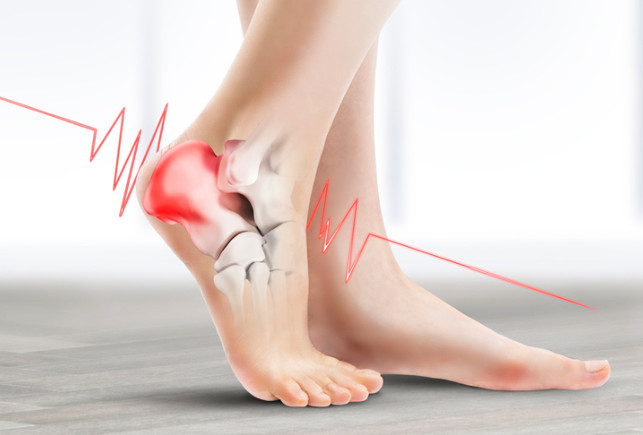

혹시 아침에 첫발을 내디딜 때 가장 아프다가 시간이 지나면 괜찮아지고, 오래 활동하면 발뒤꿈치 안쪽이 다시 아픈 경험이 있으신가요? 이는 족저 근막염일 가능성이 큽니다. 오늘은 이러한 족저 근막염 치료법에 대해 자세히 알아보겠습니다.

족저 근막염의 가장 흔한 증상은 아침에 통증이 특히 심하다는 점입니다. 밤사이 수축된 족저근막이 아침에 첫 발을 디디며 갑자기 늘어나 통증이 생기기 때문입니다. 대개 종아리 근육이 짧아지면서 발바닥 근막이 당겨져 발생하는 경우가 많습니다. 따라서 예방을 위해서는 평소 종아리와 발바닥을 함께 관리하는 것이 중요합니다. 이미 증상이 있다면 생활습관 개선과 더불어 필요에 따라 약물이나 의료적 치료를 병행해야 합니다.